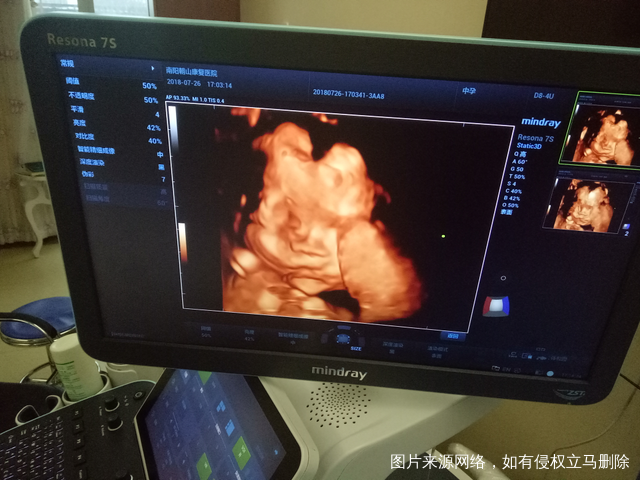

二胎四维图,大脸盘,大家猜猜是男是女,自己已知[开心]